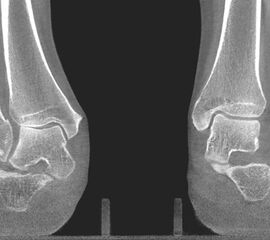

Der Computertomographie (CT) fehlt ebenfalls die Fähigkeit, den Knorpel direkt zu bewerten. Mit dem CT können jedoch weitere Details der knöchernen Verletzung, wie Größe, Form, Umfang und evtl. Dislokation der Läsion beurteilt werden 11. Insbesondere kleine Knochenkanten oder Gelenkkörper lassen sich in der CT wesentlich besser darstellen als mit einem MRT.

Zur Vollansicht und zum Lesen der Bildbeschreibung bitte das Bild anklicken.